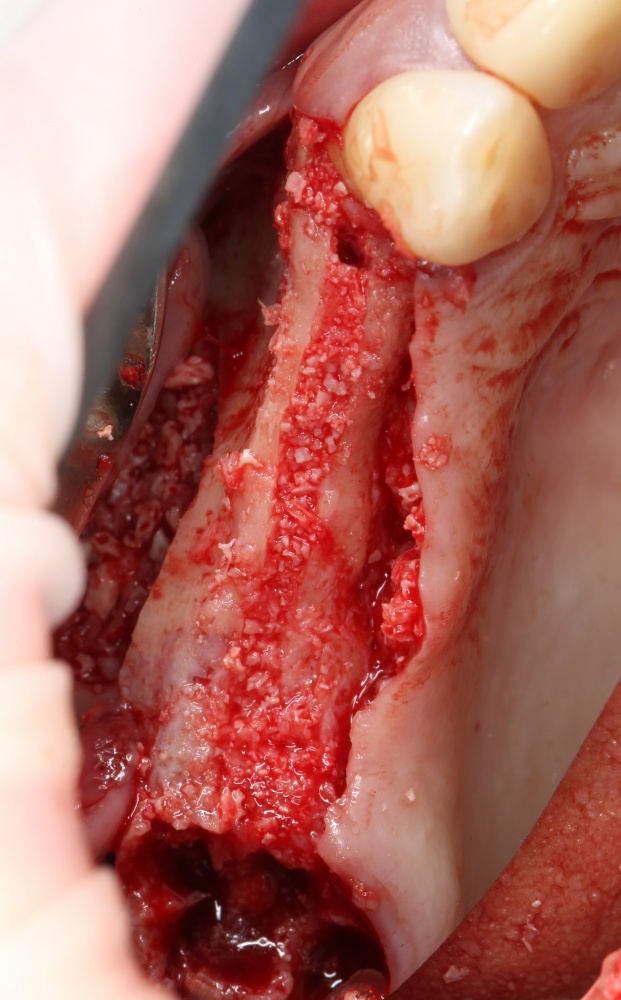

Для получения костного блока, мы открываем донорскую зону, наружную косую линию нижней челюсти.

Получение костного аутотрансплантата.

Здесь потребуется пародонтологический зонд с миллиметровой разметкой или какой-то другой измерительный прибор (операционная линейка). Ранее по КЛКТ я измерил костный дефект, теперь нужно нанести границы будущего костного блока на донорскую зону.

Ремарка: некоторые доктора предлагают делать хирургические шаблоны или выкройки специально для точного забора костного блока. На мой взгляд, это чрезмерное усложнение - во-первых, использование подобных шаблонов или выкроек требует увеличения площади раны, во-вторых, это увеличивает время и стоимость лечения, в-третьих, на этом этапе не требуется высокая точность, поскольку блок всё равно потребует адаптации.

Иными словами, важна не точность, а быстрый, аккуратный и, что главное, малотравматичный забор аутотрансплантата.

Для получения костного блока мы использовали ультразвуковую пьезохирургическую систему. Это самый удобный и безопасный инструмент для проведения подобных манипуляций. С помощью него мы сформировали и выделили костный блок. Он должен отделяться легким движением остеотома или элеватора. Как это сделать правильно — читай здесь>>